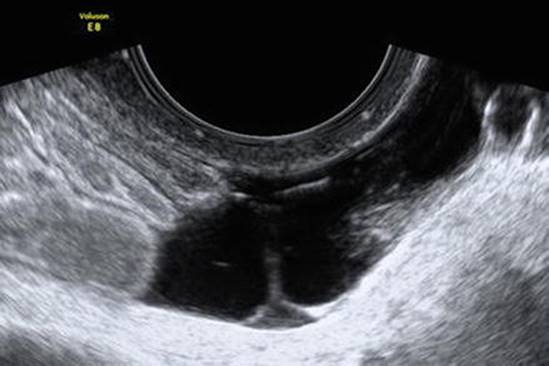

Corpus Luteum

Pelvic ultrasound reveals a small cyst, usually less than 3 cm, with thickened walls, internal echoes, crenulated (collapsing) margins, and peripheral color Doppler flow (Fig. 4.3) [6]. Follow-up for a corpus luteum measuring 3 cm or less is not required, as these most often resolve unless pregnancy occurs, at which point the corpus luteum is “rescued” to secrete progesterone that supports the pregnancy [55]. If the corpus luteum enlarges, hemorrhage into the cyst may occur, resulting in a hemorrhagic cyst (see below).

Fig. 4.3

Corpus luteum. (a) Transvaginal ultrasound reveals a 3-cm corpus luteum (calipers) with internal echoes; (b) peripheral flow is seen by color Doppler